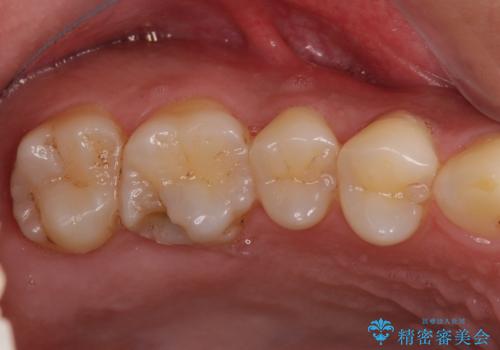

- つめものが欠けたことを主訴にご来院された患者様です。

以前、日本で保険治療をしていましたが、米国滞在中にとれて、仮の再治療をしました。その際に、中に虫歯が残っていると笑われたそうです。

今回は虫歯が大きかったものの、ぎりぎり神経に達しておらず、セラミックインレー(つめもの)の治療のみで完了しました。初診時に虫歯を除去し、後日神経のテストをして正常反応を確認しました。